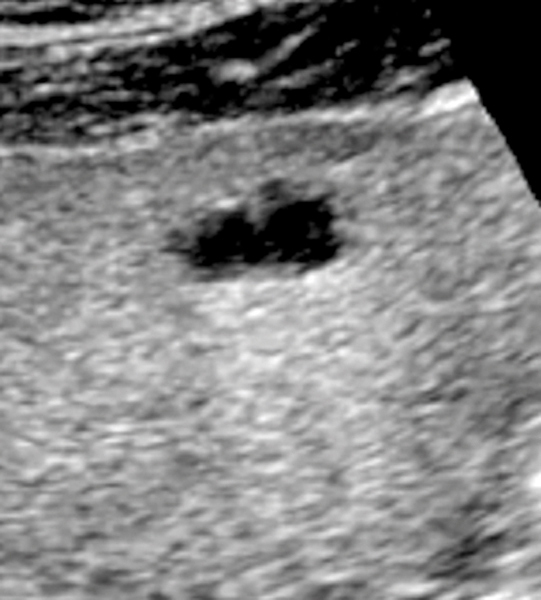

Kyste hépatique simple

Echographie. Image anéchogène avec un renforcement postérieur.